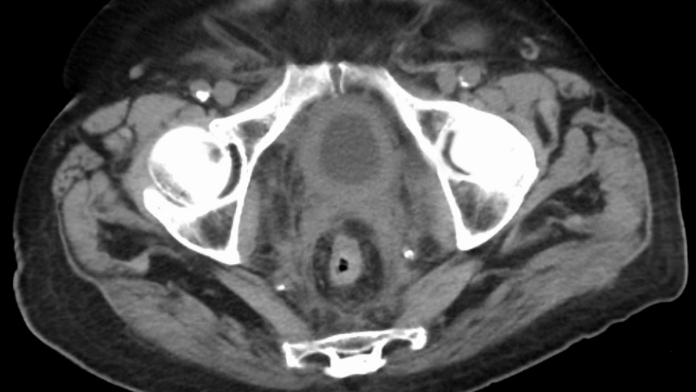

Dr Sanjai Addla, senior consultant, surgical oncology with Apollo Cancer Centre in Hyderabad, told ThePrint that the commonest form of bladder cancer is urothelial cancer, which originates in the urothelial cells that line the urinary system while less common type can include squamous cell carcinoma and adenocarcinoma.

Also, oncologists say that urothelial lining that develop malignancy in some people are present in the ureters, bladder, renal pelvis and the urethra — which is a fairly large area.